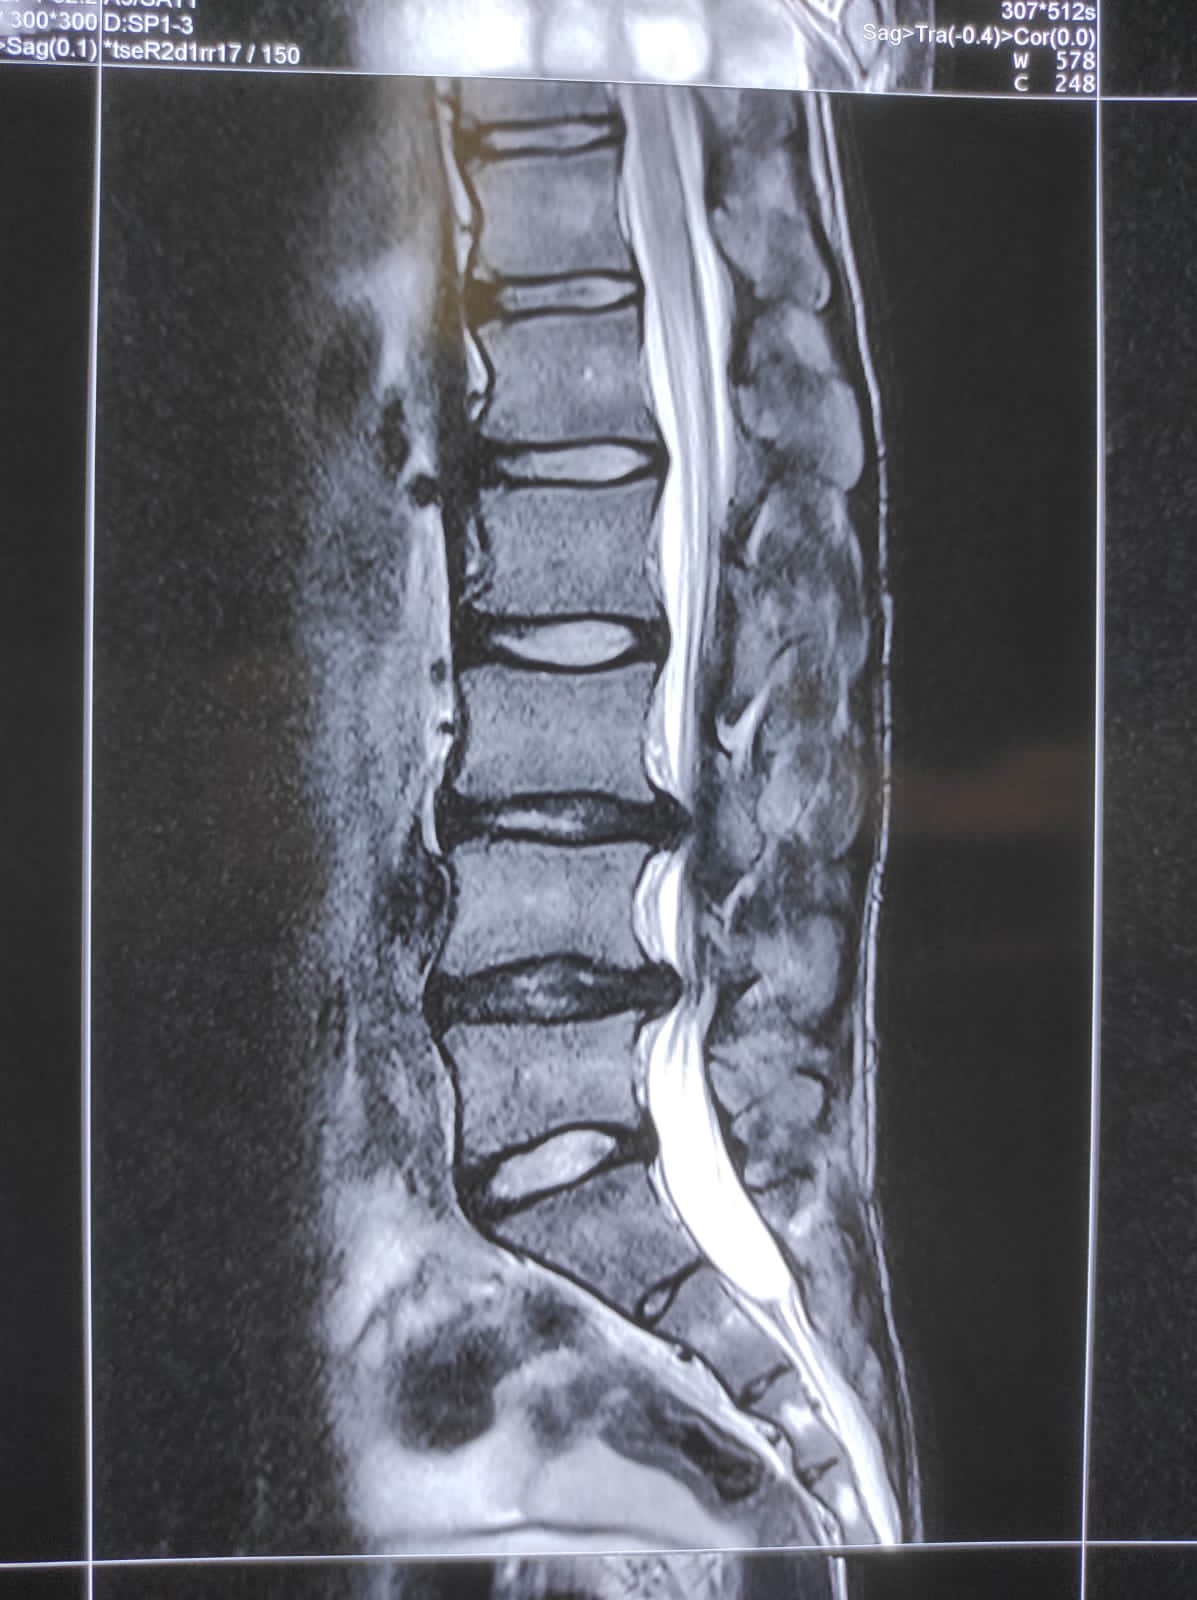

ढाडको नसा च्यापिएर र मेरुदण्डको मांशपेशी कमजोर भएर ढाड दुख्ने समस्या हुने गर्छ । मेरुदण्डको हड्डी भटेब्राले डिस्क (कुरकुरे हड्डी) लाई थिचेर कुरकुरे हड्डी बाहिर निस्किएर मेरुदण्ड हुँदै जाने नशालाई च्यापेपछि दुखाइ शुरु हुन्छ । नशा च्यापिने समस्या थोरै व्यक्तिलाई मात्र हुन्छ ।

खुट्टा झमझमाउने, लुलो हुने, दुख्ने, हिँड्न गाह्रो हुने र दिसापिसाव भएको थाहा नहुने जस्ता जटिल लक्षण देखिएमा शल्यक्रिया गर्नुपर्ने हुनसक्छ । यसका लागि एक्सरे, एमआरआई लगायतका प्रविधिबाट समस्या पहिचान गर्नुपर्छ ।